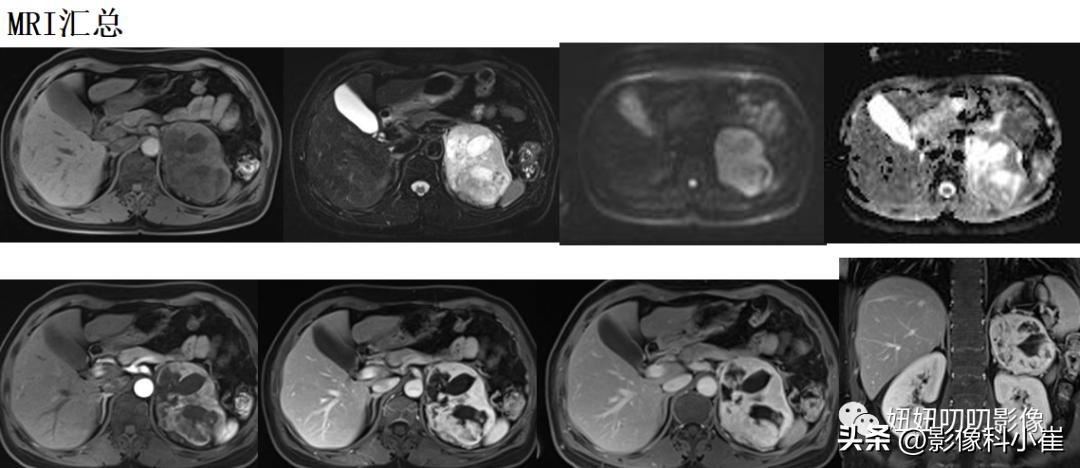

左侧肾上腺区见一团块状等长T1 等长T2 混杂信号,边界尚清,DWI示部分弥散受限,T1 反相位信号未见明显减低,最大截面约9.7X7.0X71,其内见点状短T2 信号,增强扫描呈明显渐进性不均匀强化,邻近组织受压。右侧肾上腺形态、信号未见异常,增强后未见异常强化。双肾见小圆形长T1长T2 信号,边界尚清,增强扫描未见明显异常强化。腹腔及腹膜后未见明显增大淋巴结。腹腔内未见明显液体信号灶。

见点状钙化,强化明显,T2亮,血压也升高,第一感觉还是嗜铬细胞瘤。

病理是肾上腺皮质腺瘤。